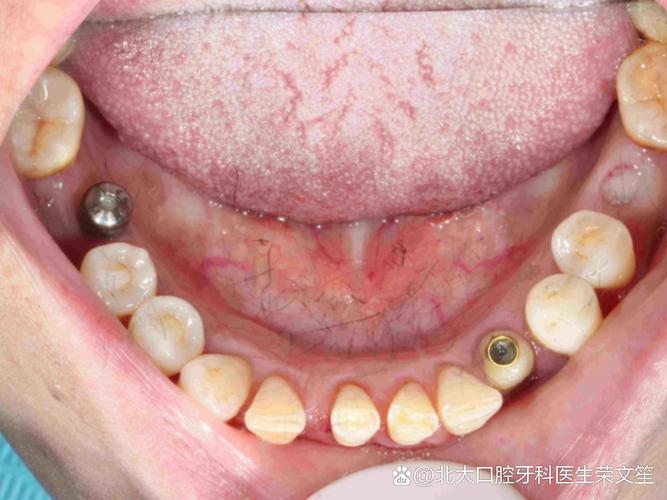

- 多颗牙缺失:对于连续2-4颗牙缺失,可植入2-3颗种植体支持固定桥,避免传统活动义齿的基牙损伤,修复效率更高。

- 基台安装与牙冠修复:骨结合完成后(3-6个月),安装个性化基台,并通过CAD/CAM技术制作全瓷牙冠,最终实现种植体的功能与美学重建。